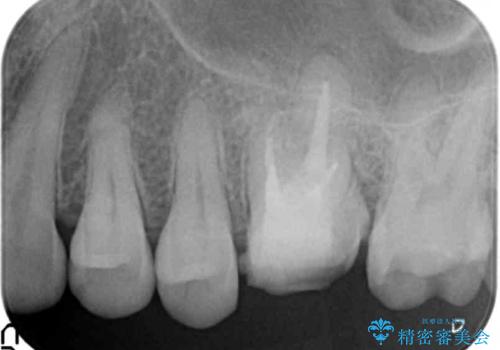

- 銀歯が取れたのち放置してしまいセラミック治療を希望され来院されました。

虫歯の再発も見られたので、丁寧に虫歯を取り除いたのち根管治療を行いジルコニアクラウン・セラミックインレーにより修復処置を行いました。

- 19.8万円(仮歯・ジルコニアクラウン・セラミックインレー)費用は治療当時の料金となります